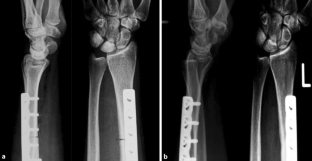

Abb. 2